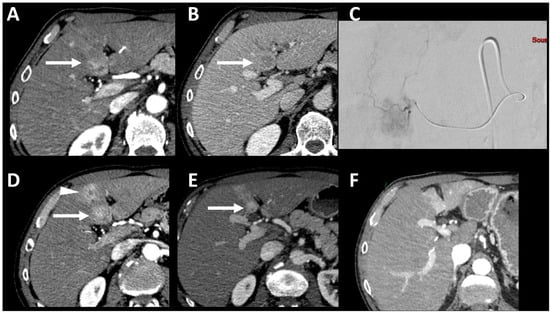

- Dioguardi Burgio, M.; Ronot, M.; Bruno, O.; Francoz, C.; Paradis, V.; Castera, L.; Durand, F.; Soubrane, O.; Vilgrain, V. Correlation of tumor response on computed tomography with pathological necrosis in hepatocellular carcinoma treated by chemoembolization before liver transplantation. Liver Transplant. 2016, 22, 1491–1500. [Google Scholar] [CrossRef] [PubMed]

- Dioguardi Burgio, M.; Sartoris, R.; Libotean, C.; Zappa, M.; Sibert, A.; Vilgrain, V.; Ronot, M. Lipiodol retention pattern after TACE for HCC is a predictor for local progression in lesions with complete response. Cancer Imaging 2019, 19, 75. [Google Scholar] [CrossRef] [PubMed]